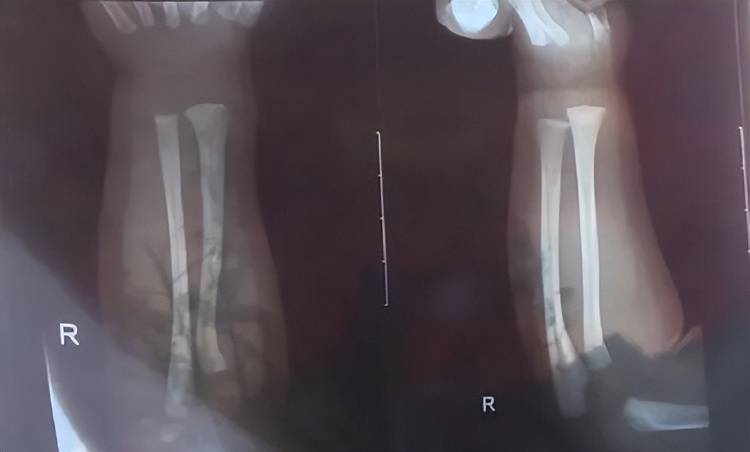

次日上午,孩子被带到附近医院检查,医生诊断发现他右手有两处骨折,第一处为右侧尺骨远端骨折,第二处为右侧桡骨远端骨折,随后医生给他做了石膏固定,“没想到,几天后孩子还被诊断出脑电图异常,医生建议复查虚拟币挖矿程序原理。”

孩子被诊断发现两处骨折